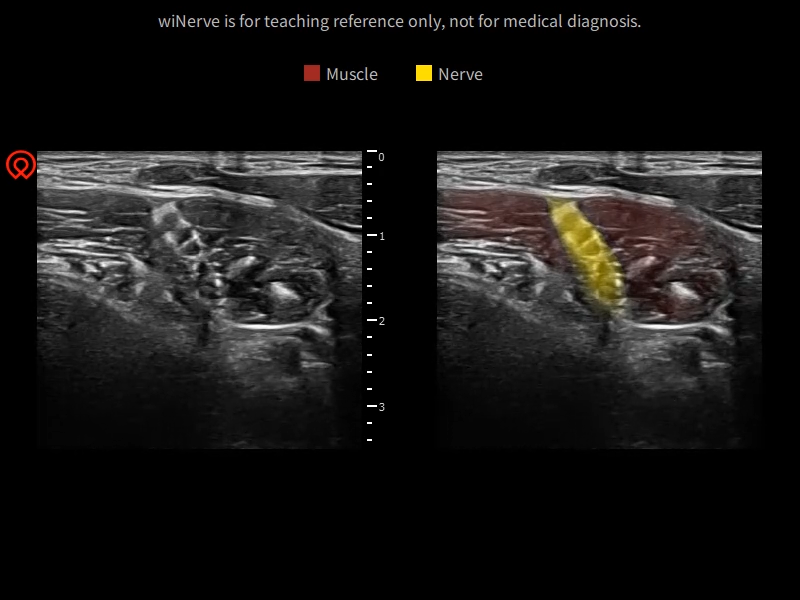

wiNerve - Reconnaissance intelligente des nerfs par IA

Reconnaissance en temps réel

Solution Cloud

Soutenir plusieurs nerfs